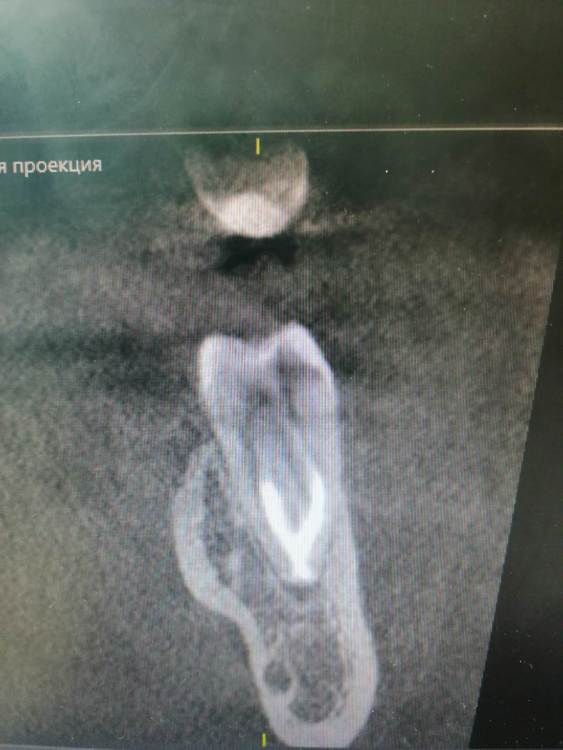

Тильда Опубликовано 30 апреля, 2021 Поделиться Опубликовано 30 апреля, 2021 (изменено) Коллеги, очень нужен ваш совет. В октябре 2020 года проведено эндо лечение 4.6 по диагноз пульпит хронический. Лечение было проведено в одно посещение, ирригант - гипохлорит, M-Two до 30 медиальные и до 40 дистальный, вертикальная конденсация. Недавно (через пол года после лечения) пациентка обратилась снова с жалобами на боли в области пролеченного ранее зуба. Причём причинный зуб локализует чётко. Боли появились сразу после лечения, постепенно немного стихли, но полностью не болит. Болит при механическом раздражение вестибулярной стенки, по словам пациентки отдаёт по челюсти. Перкуссия и термо проба безболезеннные. Слизистая без особенностей. На одном из срезов КТ можно заподозрить расширение периодонтальной щели в периапикальной области медиальных корне, но вроде бы и до лечения картина похожая. Есть ли смысл сделать повторное эндо? Буду благодарна за ваши мысли по поводу дальнейшей тактики. Извиняюсь за качество снимков и понимаю, что их сложно оценить Изменено 30 апреля, 2021 пользователем Тильда Ссылка на комментарий